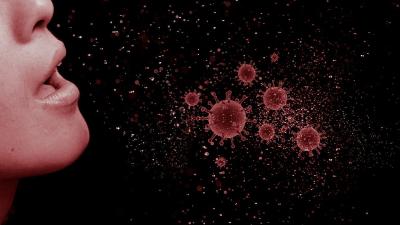

Coronavirus : खोकल्याने किंवा शिंकल्याने बाहेर आलेले मायक्रोस्कोपिक ड्रॉपलेट्स साधारण 3 तास हवेत आपला प्रभाव दाखवू शकतात.

कोरोना व्हायरस ड्रॉपलेटच्या माध्यमातून संक्रमित व्यक्तीतून दुसऱ्या व्यक्तीमध्ये पसरतो. त्यामुळे खोकताना किंवा शिंकताना तोंडावर हात ठेवण्याचा किंवा मास्क घालण्याचा सल्ला दिला जातो.

वैज्ञानिकांनी सांगितले की, खोकल्याने किंवा शिंकल्याने बाहेर आलेले मायक्रोस्कोपिक ड्रॉपलेट्स साधारण 3 तास हवेत आपला प्रभाव दाखवू शकतात.

पण हवेत असलेले अर्ध्यापेक्षा अधिक व्हायरस पार्टिकल्स साधारण 66 मिनिटात निष्क्रिय होतात. तेच व्हायरसचे साधारण 25 टक्के पार्टिकल्स साधारण एक तास अॅक्टिव राहतील.

तिसऱ्या तासात यांची संख्या कमी होऊन 12.50 टक्के इतकी राहिल. कोरोना व्हायरस तांब्याच्या वस्तूवर कमी सक्रिय राहतो. साधारण 46 मिनिटात तांब्यावर याचा अर्ध्यापेक्षा जास्त प्रभाव कमी होतो.